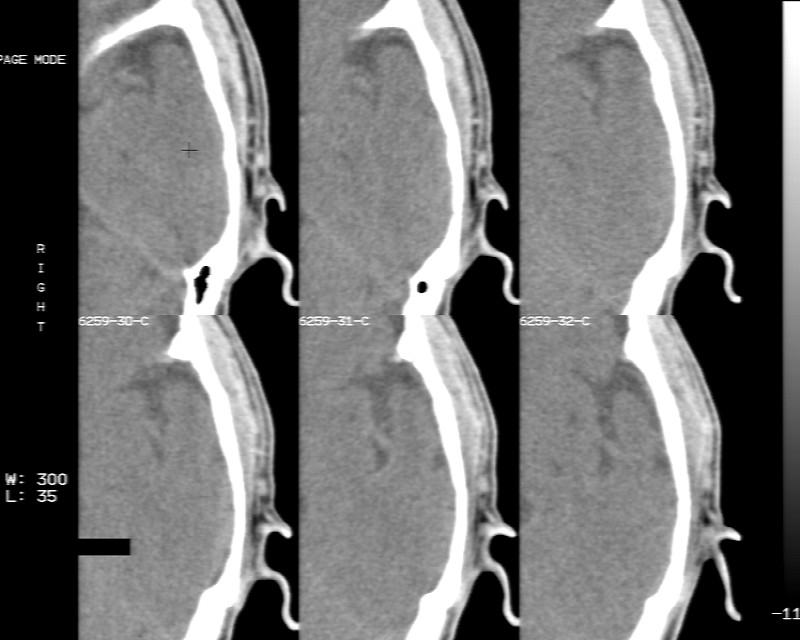

m70y, 2个月前发现左颞部有'包'隆起,近来自觉增大,无外伤无任何不适症状而就医,触诊包块质地较硬无移动无波动无皮温升高,胸片示右上肺陈旧结核....,ct扫描见左颞骨翼板局部内外骨板骨质破坏,似筛孔状,外板侧有骨膜线状增生,伴局部软组织丘状肿块,内板下梭形肿胀硬膜增厚翘起......颅内脑无异常.考虑骨良性病变 1.低度骨感染.   2.嗜酸性肉芽肿. 3.不排外骨结核...建议其穿刺活检,但患者失踪,追踪到结果定将公告.请大家分析.

左颞骨内板不光滑,密度减低,内板下可见新月形的软织密度影。脑实质轻度受压,外板外见膨胀形稍高密度影。考虑嗜酸性肉芽肿。建议增强扫描

考虑为骨感染,颅内脑实质受压,颞部头皮软组织肿胀

骨质密度不均,骨质两旁均有软组织影,考虑嗜酸性肉芽肿可能性大,同时也不能除外转移瘤。

除了以上的诊断,大家不考虑转移瘤吗,病人有陈旧结核,合并瘢痕癌呢,并发颅骨转移,肺癌发生骨转移的几率要比其它恶性肿瘤大的多,虫蚀样的骨质破坏就是良性病变吗,我考虑转移瘤。